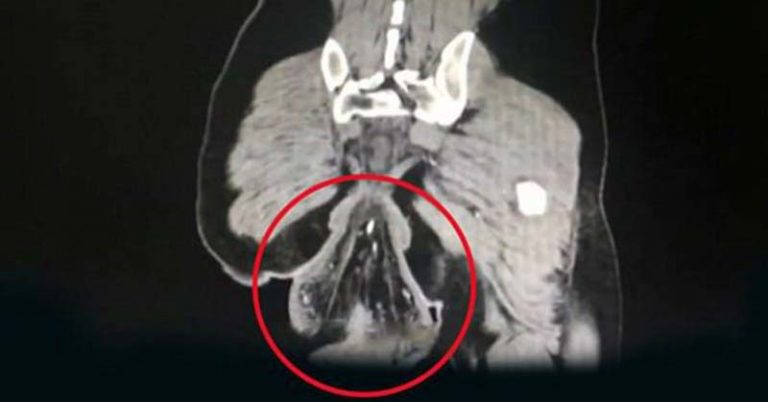

There is a painful disease that takes place amongst many women. Endometriosis is a common and sometimes debilitating condition experienced by women of reproductive age, it is estimated to affect 10% of women. This disease can cause chronic pelvic pain and is sometimes associated with infertility. Misplaced endometrial tissue is what defines endometriosis. Typically, endometrial...